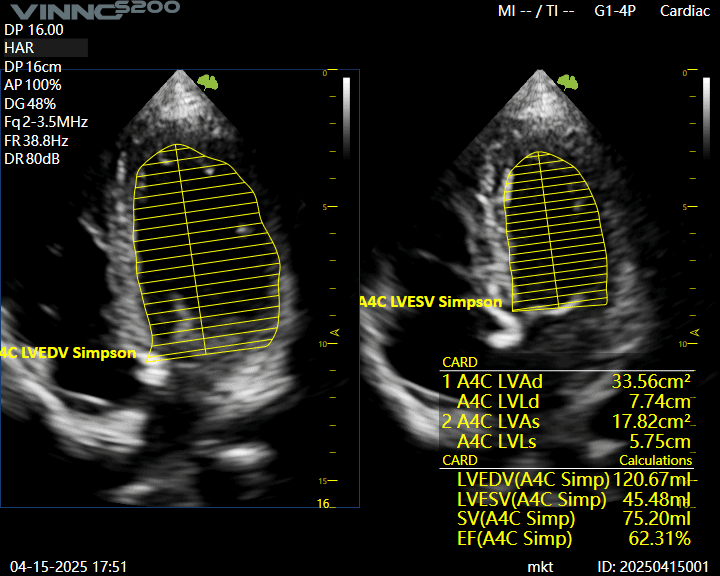

Ecograful VINNO S200 este versatil si performant, recomandat clinicilor care au nevoie de un echipament fiabil pentru diverse specialitati: interne, gastroenterologie, ginecologie, ecografie generala etc.

- Functii avansate precum module cu AI, elastografie si Doppler color de inalta rezolutie

Citeste mai multEcograf VINNO S200 – solutie moderna pentru evaluari zilnice

Ecograf VINNO S200 – solutie moderna pentru evaluari zilnice Echipa Numeris Medical a finalizat cu succes instalarea ecografului VINNO S200 in cabinetul domnului dr. Ipate Florin, medic specialist cardiologie din Calarasi.In cardiologie, claritatea imaginii, stabilitatea semnalului si sensibilitatea Doppler sunt…